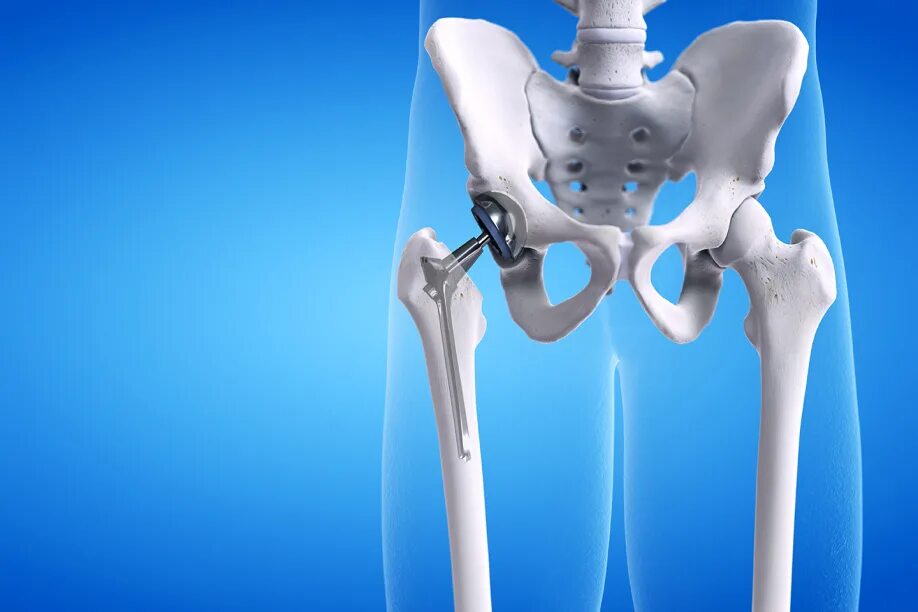

Протезы тазобедренных суставов по квоте